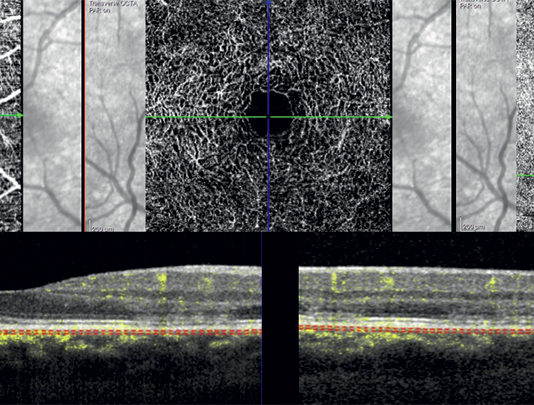

Aggiornamenti su optical coherence tomography angiography: miglioramenti conseguiti e prospettive future

Negli ultimi anni la metodica nota come optical coherence tomography angiography (OCTA) ha aperto nuove strade nell’imaging...